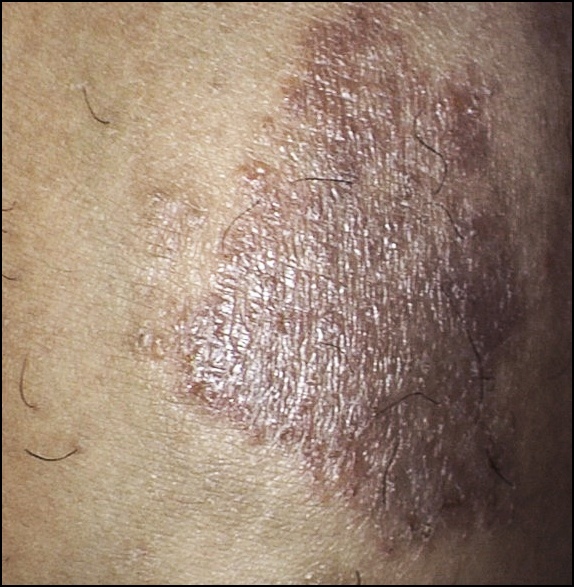

지루성피부염 병원치료 없이 홈케어로 치료한 후기

지루성피부염 병원치료 없이 홈케어로 치료한 후기 지루성피부염 병원치료 없이 홈케어로 치료한 후기 지루...